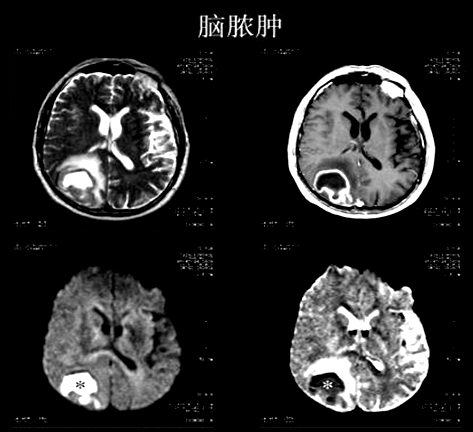

2、感染性病变与肿瘤性病变鉴别诊断

①脑脓肿:脓腔于DWI呈均匀高信号,ADC低信号--弥散受限,与脓液的高粘滞度和脓肿的多细胞性有关。